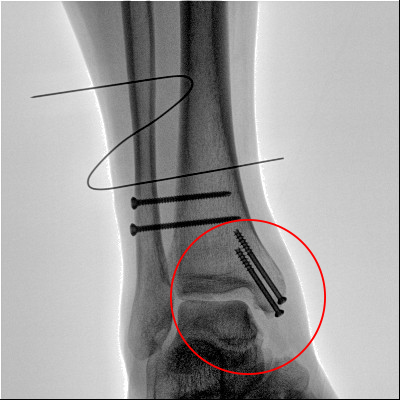

踝關節(jié)骨折在X影像上的表現(xiàn)有很多種。如內踝骨折和外踝骨折,我們可以在影像上看到骨折處的骨折線是不連續(xù)的。還有后踝的骨折,內踝、外踝、后踝聯(lián)合在一起發(fā)生的骨折,我們稱之為“三踝骨折”,這些都是在X影像上能夠顯示出來的。

內踝骨折

外踝骨折

后踝骨折

三踝骨折